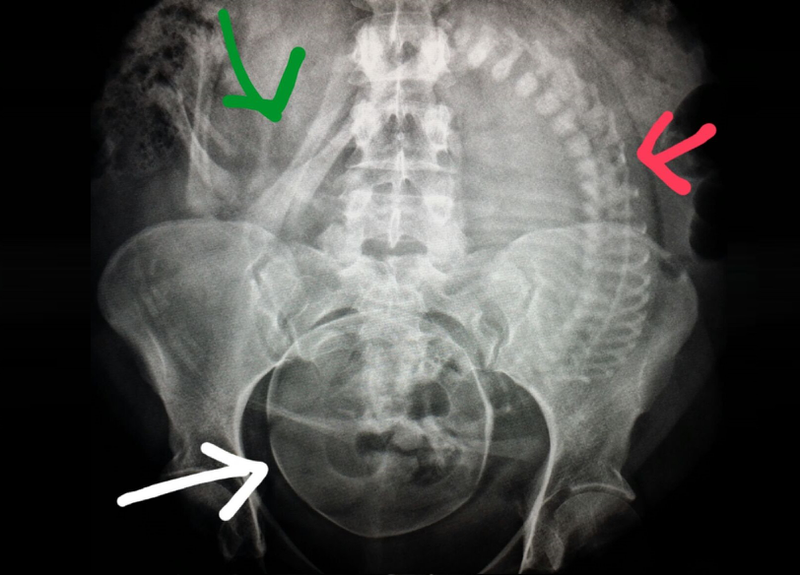

• Chụp X-quang: Cấy ghép Implant đòi hỏi phải chụp X-quang (CBCT) trước, trong và sau quá trình cắm Implant. Tia X có thể ảnh hưởng đến thai nhi. Do đó, tuyệt đối không được can thiệp nha khoa nói chung và Implant nói riêng trong giai đoạn mang thai.

phụ nữ mang thai không nên cấy implantHình ảnh thể hiện tia X xuyên qua các bộ phận